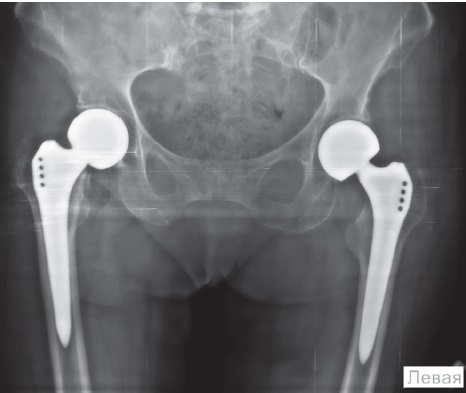

На следующий день после госпитализации, 15.10.2021, в одну операционную сессию последовательно из переднелатеральных хирургических доступов было выполнено эндопротезирование правого, а затем левого тазобедренного сустава. Были установлены модульные монополярные эндопротезы бесцементной фиксации отечественного производства. Продолжительность операционной сессии: артропластика правого тазобедренного сустава — 35 мин., левого — 32 мин. С учетом повторного укладывания пациентки при смене стороны операции общее время операции достигло 77 мин., объем общей кровопотери составил около 250 мл. На послеоперационной рентгенограмме тазобедренных суставов от 15.10.2021 в прямой проекции положение компонентов эндопротезов удовлетворительное (рис. 2).

Рис. 2. Рентгенография таза пациентки после операции: положение компонентов эндопротезов удовлетворительное

Figure 2. Patient’s pelvic X-ray after the surgery: position of the endoprostheses components is satisfactory